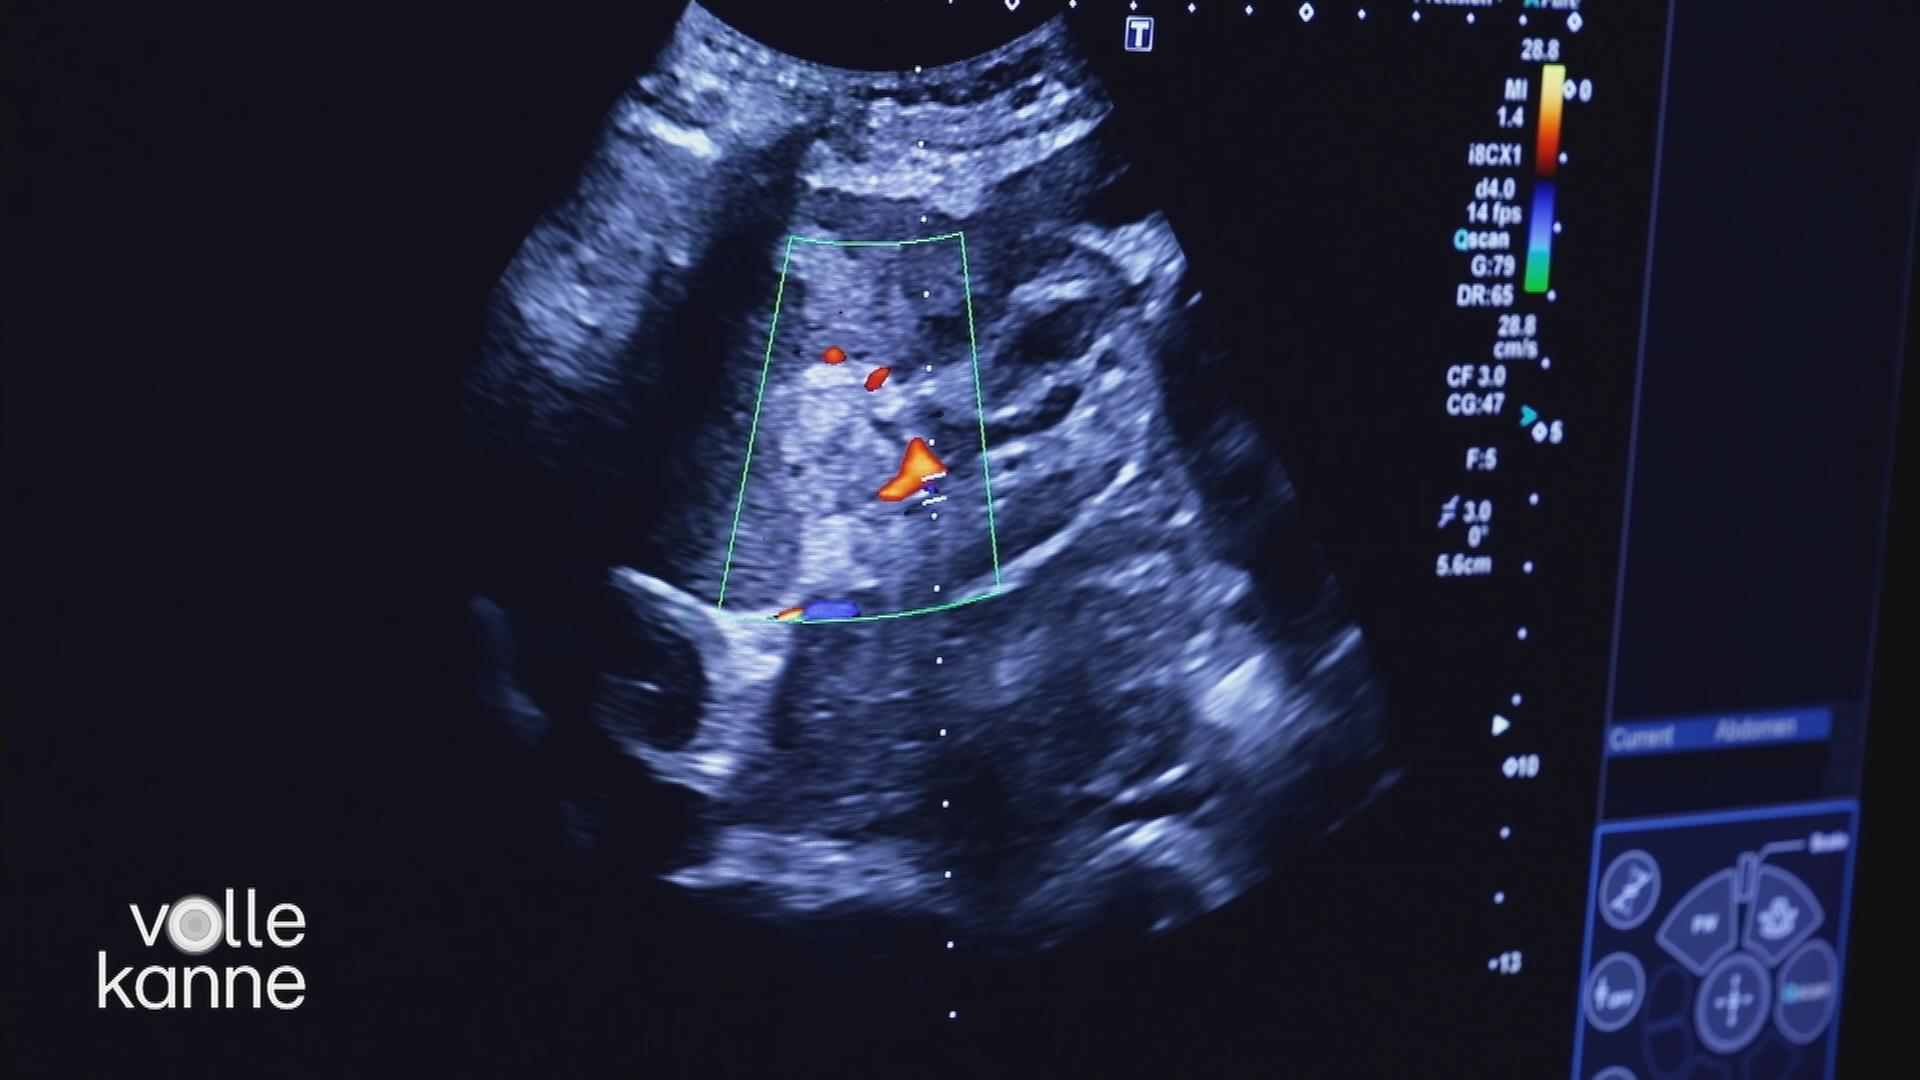

Die Nieren sind wahre Multitalente und für unser Leben unverzichtbar. Wenn sie nicht mehr funktionieren, gibt es jedoch kaum eine Lösung. Was bedeutet eine chronische Nierenerkrankung für Betroffene?